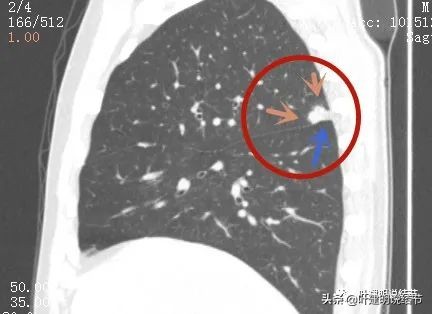

我们再来看薄层的CT图像:

病灶出现,虽然此层面还很小,但也是实性的,有微血管进入(桔色箭头)

上图更清楚显示血管进入病灶,病灶与胸膜间点状相接,感觉病灶有膨胀性,圆形或类圆形的

病赤边缘不平整,感觉毛糙(紫色箭头),此层也见血管征(桔色箭头)

病灶边缘不平,略模糊

边缘似见少许磨玻璃成分(绿色箭头),病灶与胸壁间离的这么近,但有低密度分界(黄色箭头),说明不是普通炎症性,如果炎症会有水肿,间隙一般不清

上图除了间隙以外,病灶有的地方有膨胀性,往外鼓出去一点(砖色箭头)

膨胀性以及与胸壁间隙

上图示病灶边缘毛糙(紫色箭头),以及与胸壁间的间隙存在(黄色箭头)

病灶边缘欠平整

叶间裂受到牵拉(蓝色箭头)

也示叶间裂牵拉

病灶边缘部位